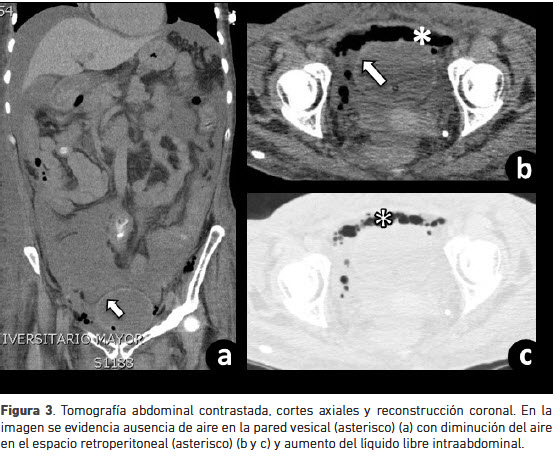

Por lo anterior es trasladada a la unidad de cuidados intensivos, en donde se le inició manejo con milrinone y se adicionó vancomicina al manejo antibiótico. Se realizó nueva tomografía abdominal simple de control a los 10 días pos-tratamiento que evidenció disminución del neumoretroperitoneo y del enfisema de tejidos blandos pélvico (figura 3).

Los dos casos reportados de retroneumoperitoneo fueron inicialmente manejados con antibióticos endovenosos y cateterización uretral, como en el caso descrito. Uno de éstos requirió manejo quirúrgico, debido al hallazgo de necrosis de la pared vesical en la tomografía de abdomen de control a los siete días (1,2).